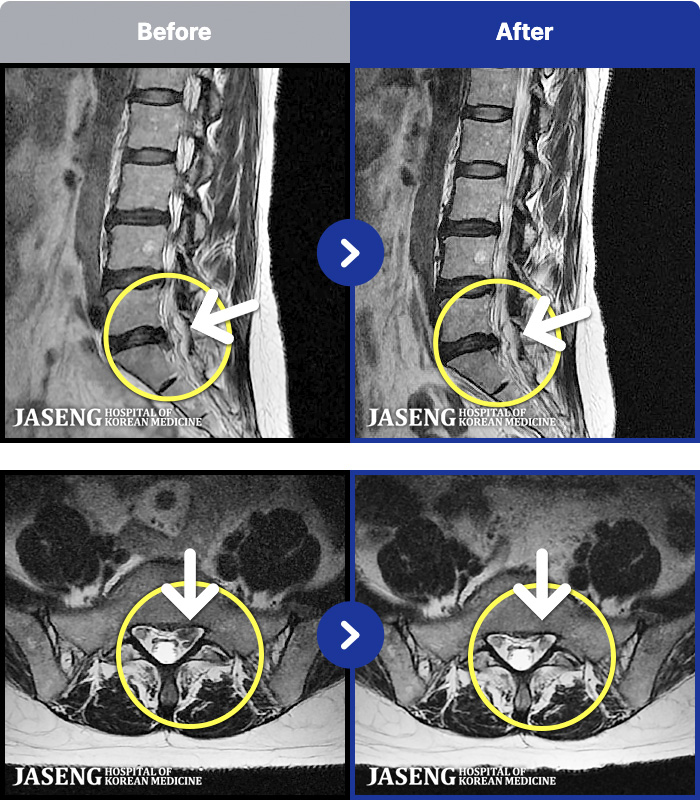

[Կñ:21.12.17~22.07.04]

[_㸮ũ] 㸮

No.53

ȸ 212

2026.01.09